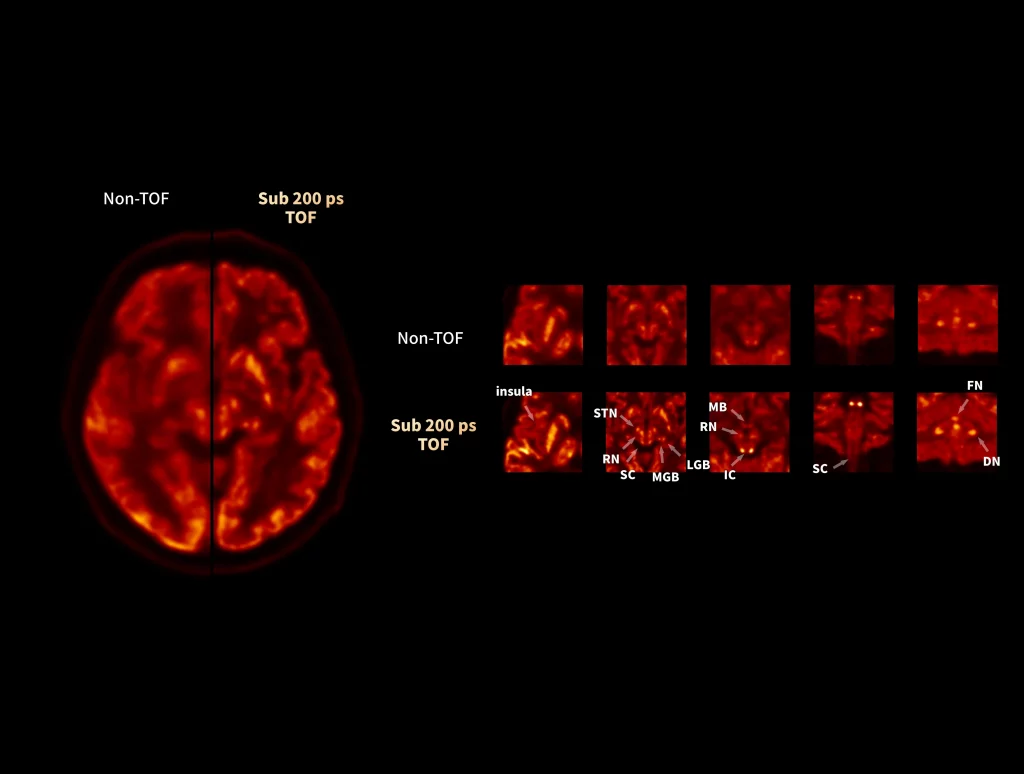

uMI Panorama is clearly magnificent in every direction with the finest National Electrical Manufactures Association (NEMA) PET spatial resolution, truly-fast 189-picosecond (ps) time of flight (TOF), scalable axial field of view (AFOV), the 76-cm super-wide bore and 318-kg (700-lb) table weight capacity that accommodates patients of all sizes.1 By leveraging the AI-powered features on the uExcel platform, it also boosts your daily work efficiency significantly and opens up new possibilities for your exploration.

uMI Panorama is greatly empowered by innovative technologies integrated into the uExcel SCAN and uExcel CARE workflows. With uExcel SCAN, you can rely on intelligent positioning, scanning, and motion correction to streamline your routine tasks and maximinze your work efficiency. And uExcel CARE features uExcel DPR and uExcel AIIR reconstruction algorithms to ensure clear images even at low doses.

Unlock New Possibilities for Exploration